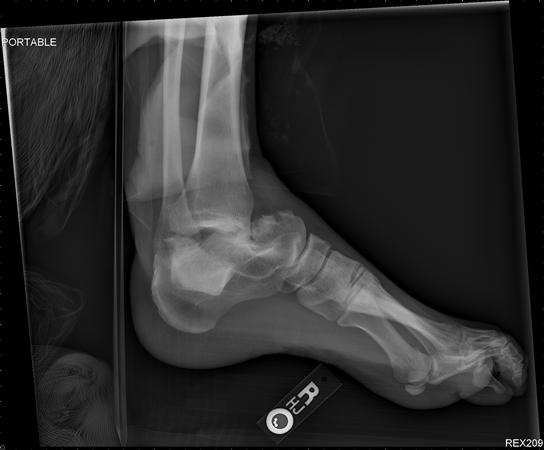

- Radiographs

- recommended views

- AP

- lateral

- Canale view

- best view to demonstrate talar neck fractures

- technique is maximum equinus, 15 degrees pronated, xray 75 degrees cephalad from horizontal

- CT scan

- best study to determine degree of displacement, comminution and articular congruity

- CT scan also will assess for ipsilateral foot injuries (up to 89% incidence)